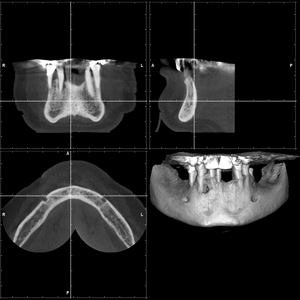

L’implantologia dentaria si occupa di sostituire i denti mancanti utilizzando viti in titanio nell'osso.